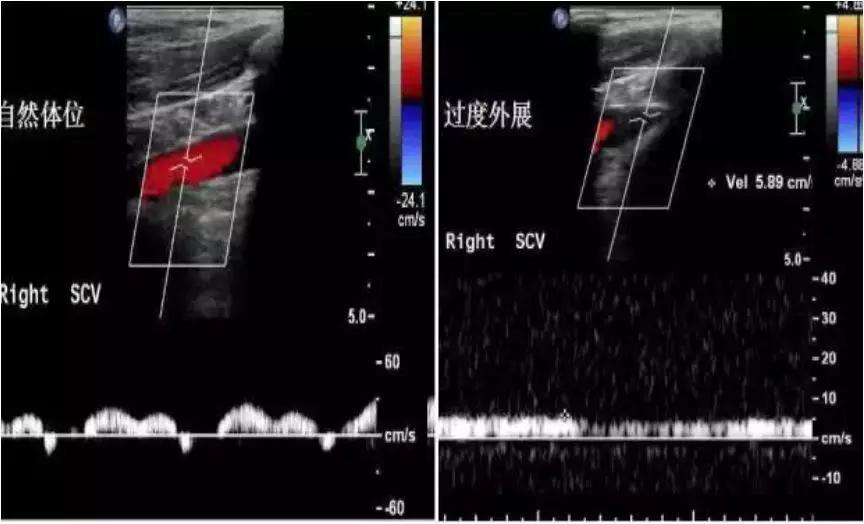

(左图)自然体位:锁骨下静脉受呼吸影响的正常期相频谱;(右图)上举体位:锁骨下静脉不受呼吸影响(进一步提示本病!)